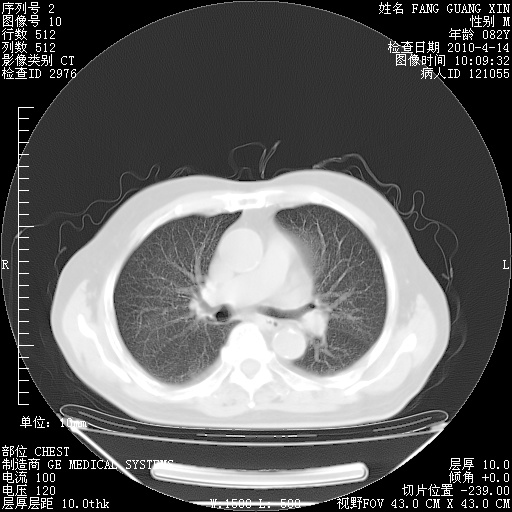

肺部CT平扫未见异常。